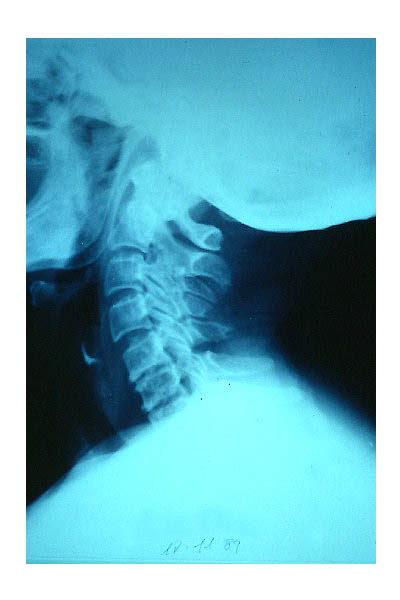

Artrosis cervical.

Artrosis cervical

APR Cervicoartrosis